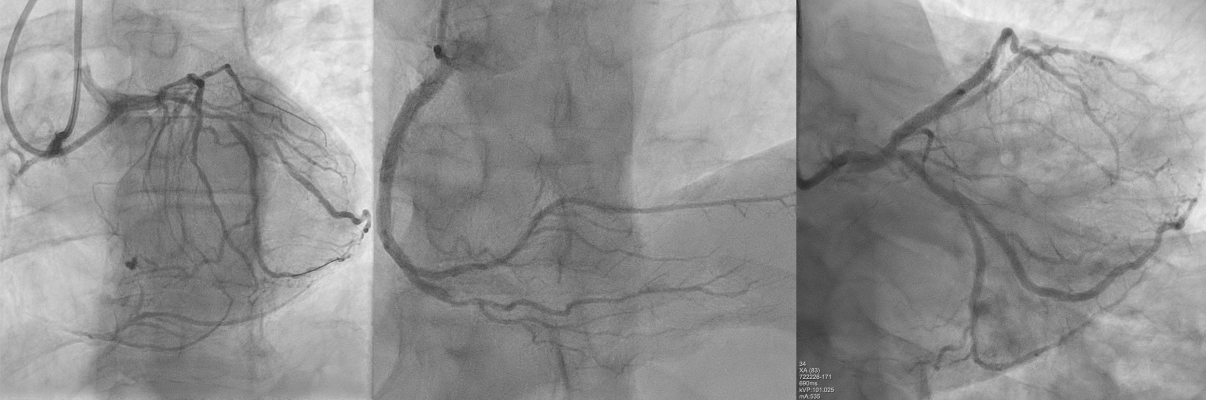

Διαγνωστική στεφανιογραφία: Πρόκειται για ελάχιστα επεμβατική πράξη, κατά την οποία μετά από παρακέντηση είτε της κερκιδικής αρτηρίας (χέρι) είτε της μηριαίας αρτηρίας (πόδι), ειδικά διαμορφωμένος λεπτός καθετήρας εισέρχεται στο στόμιο των στεφανιαίων αρτηριών διαμέσου του οποίου πραγματοποιείται εκλεκτική έγχυση σκιαγραφικής ουσίας εντός του αυλού των στεφανιαίων αγγείων.

Η ακτινοσκοπική-αγγειογραφική απεικόνιση του αυλού των αγγείων μέσο της σκιαγραφικής ουσίας επιτρέπει την απεικόνιση του αυλού των αγγείων με μαύρο χρώμα επιτρέποντας έτσι την ανάδειξη ενδοαυλικών στενώσεων ή πλήρους απόφραξης των στεφανιαίων αρτηριών. Με τη στεφανιογραφία δύναται να χρησιμοποιηθούν και άλλες επεμβατικές διαγνωστικές μέθοδοι, όπως η κλασματική εφεδρεία ροής (Fractional Flow Reserve – FFR) και τεχνικές ενδοαγγειακής απεικόνισης (ενδοαγγειακό υπερηχογράφημα, οπτική συνεκτική τομογραφία), οι οποίες επιτρέπουν την διάγνωση σημαντικών στενώσεων με σχεδόν απόλυτη ακρίβεια.

Επιπλέον, μετά την στεφανιογραφία υπάρχει η δυνατότητα ad hoc παρέμβασης και θεραπείας των στενώσεων με την διενέργεια της αγγειοπλαστικής και της τοποθέτησης ενδοστεφανιαίων προθέσεων (stents)